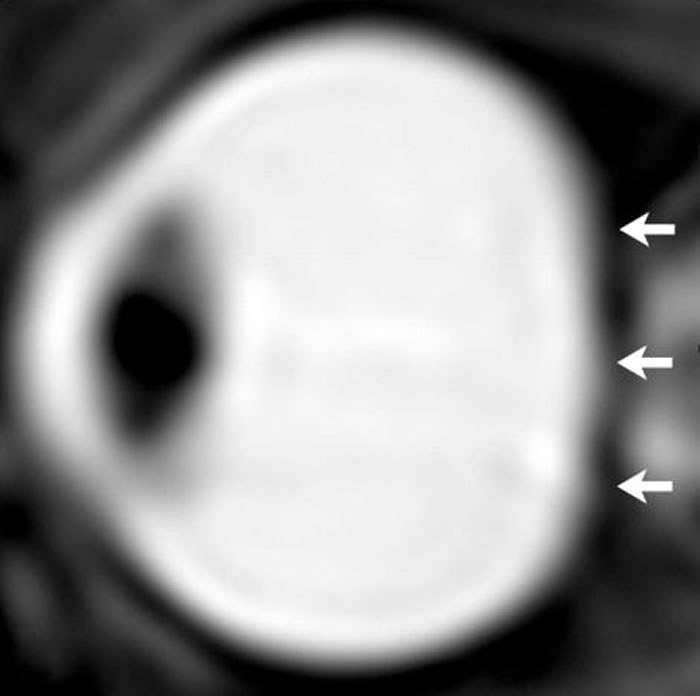

太空人眼部的核磁共振图。在长期的太空生活之后,太空人的眼球出现被挤压扁平的状况。 PHOTOGRAPH BY RSNA

太空旅行将会搅乱这个系统,因为在微重力的环境中并没有许多需要因变换姿势而改变脊髓液压力的情况。在对七名太空人在长期太空旅行前后进行核磁共振扫描后,阿鄱林和同僚得到了这个结论;他们还将另外九名进行短期太空任务的太空人的测试结果进行比较。

他们发现在太空中待上数月的七名太空人的眼窝内普遍发现较多量的脑脊髓液。这让太空人眼球后方承受了更多压力,造成眼球后方挤压,进而导致视神经突出。